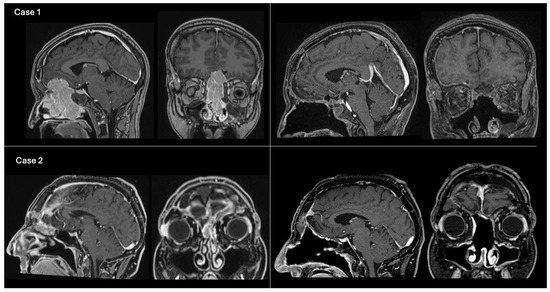

Figure 2. Example cases of preoperative and postoperative T1-weighted contrast-enhanced brain MRI. Case 1 (above): On the left, preoperative MRI on sagittal and coronal views showing an olfactory neuroblastoma (grade C, modified Kadish classification [15]) invading the anterior cranial fossa. The ASB was reconstructed using method 1 (pericranial flap + overlay fascia lata graft). The NSF was not available due to tumor invasion of the nasal septum mucosa. On the right, 1-month postoperative MRI showing gross total resection of the tumor. Case 2 (below): On the left, preoperative MRI on sagittal and coronal views depicting a recurrent ASB atypical meningioma (Grade 2, WHO 2021), previously operated via open approach, with unilateral extension into the right nasal fossa. The ASB was reconstructed using method 2 (pericranial flap + fascia lata graft + NSF). On the right, 2-year postoperative MRI in sagittal and coronal views, demonstrating total tumor removal and intact ASB reconstruction following adjuvant RT.

All patients underwent preoperative brain computed tomography (CT) scan and contrast-enhanced magnetic resonance imaging (ce-MRI). The indications for a CEA were as follows: intracranial tumors of the ASB infiltrating the nasal fossae, paranasal sinuses and orbits; sinonasal malignancies filling the frontal sinus or invading the ASB with intradural extension over the orbital roof and/or frontal lobes invasion (pT4a-T4b, N0, M0) [13] (Figure 2); post-traumatic ASB fractures with CSF leak; and post-surgical encephalocele. Exclusion criteria were pure endoscopic endonasal approaches or transcranial approaches.

Regarding anterior skull base reconstruction (Figure 1), Group 1 consisted of 40 patients (86.9%), including all cases of S(2) and 38 oncologic cases S(1). Group 2 included 6 patients (13.1%), comprising the S(3) cases and 4 oncologic cases S(1): specifically, 3 cases of ASB meningiomas with unilateral nasal extension and 1 case of unilateral spinocellular carcinoma (SCC).